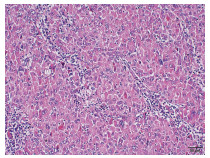

Successful treatment of Bouveret ' s syndrome due to giant duodenal gallbladder stones through the anterior wall of the stomach: A case report

Xu CHEN, Lunxu LI, Bing QI, Qingkai ZHANG, Guixin ZHANG, Shuang LI, Dong SHANG

2022, 38(3): 636-638. DOI: 10.3969/j.issn.1001-5256.2022.03.028

Abstract(974) HTML (241) PDF (2628KB)(64)

Abstract: